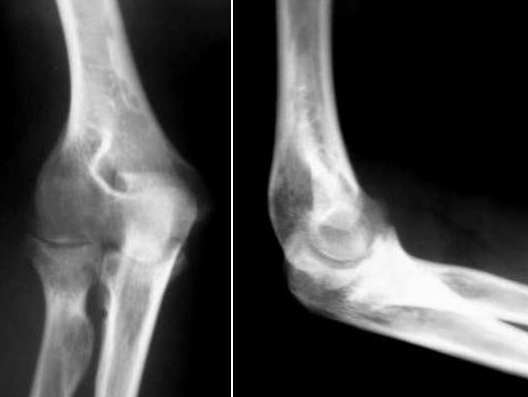

女,21岁,半年前有过发热38℃,之后左肘部肿胀疼痛,关节屈曲功能障碍,

同时临床医生检查腕关节僵直。类风湿(—) 血沉加快 .右手检查无明显异常

肘关节间隙变窄,关节面毛糙(不知软组织窗是否有关节积液显示?)。结合腕关节强直及血沉加快,考虑关节tb(滑膜型)可能。

肘关节部分骨质破坏,部分边缘硬化,骨质周围边缘毛糙,可以上传软组织窗,考虑结核病变

左肱骨下端外上髁,左尺骨鹰嘴背侧,左桡骨小头见斑片状骨质密度减低区,以骨质破坏为主,考虑左肘关节结核.应参考实验室检查.

航书说:左肱骨下端外上髁,左尺骨鹰嘴背侧,左桡骨小头以骨质破坏为主,应当上传软组织窗,观察软组织改变情况。再问病史有无低热盗汗。应参考实验室检查。考虑左肘关节结核.